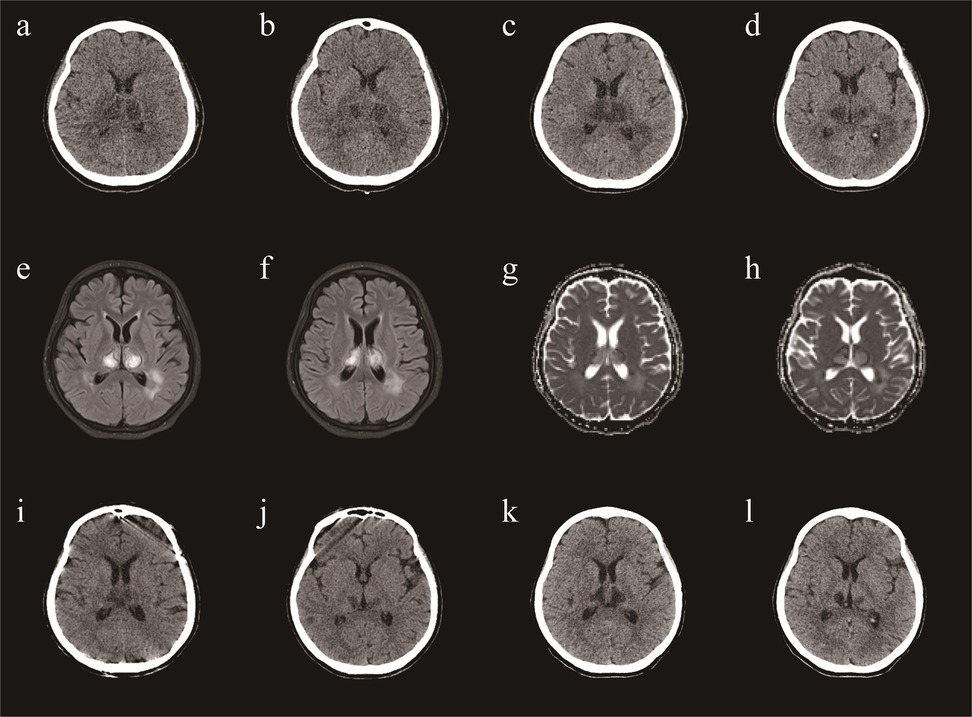

Brain Computed Tomography (CT) and Magnetic Resonance Imaging (MRI) revealed lesions involving the bilateral striatum, thalamus, and brainstem, typical for ANE (Figures 1A,B,I–L). A diagnosis of ANE accompanied by fulminant myocarditis was considered. Therefore, tocilizumab was included in the treatment regimen. Tocilizumab was used in hospital day 9 (8 mg/hg of tocilizumab for 1day). On the tenth day of admission, the patient began to regain consciousness. She was transferred to a general ward after 13 days. Echocardiography showed a significant improvement in left ventricular function (EF = 61%). The patient was discharged after approximately 24 days of rehabilitation. At the time of discharge, the patient could walk and speak clearly. She was discharged with a prescription for cardioprotective agents, including metoprolol, sacubitril/valsartan, spironolactone, furosemide, and dapagliflozin. One month after discharge, the patient was able to walk on her own, her speech was cleared, there were no remaining symptoms, and her heart function was normal. A repeat CT revealed that the lesions in the head had reduced (Figures 1G,H).

Figure 1

A brain CT (a,b) demonstrating symmetric lesions involving thalami, striatum and brain stem, consistent with acute necrotizing encephalopathy in day 12. A repeat CT revealed that the lesions in the head had reduced (c,d) in day 20. A repeat CT revealed that the lesions in the head had reduced (e,f) in day 38. One month after discharge, a repeat CT revealed that the lesions in the head had reduced (g,h). MRI (i,j) demonstrating symmetric lesions involving thalami, striatum and brain stem, consistent with acute necrotizing encephalopathy in day 22.